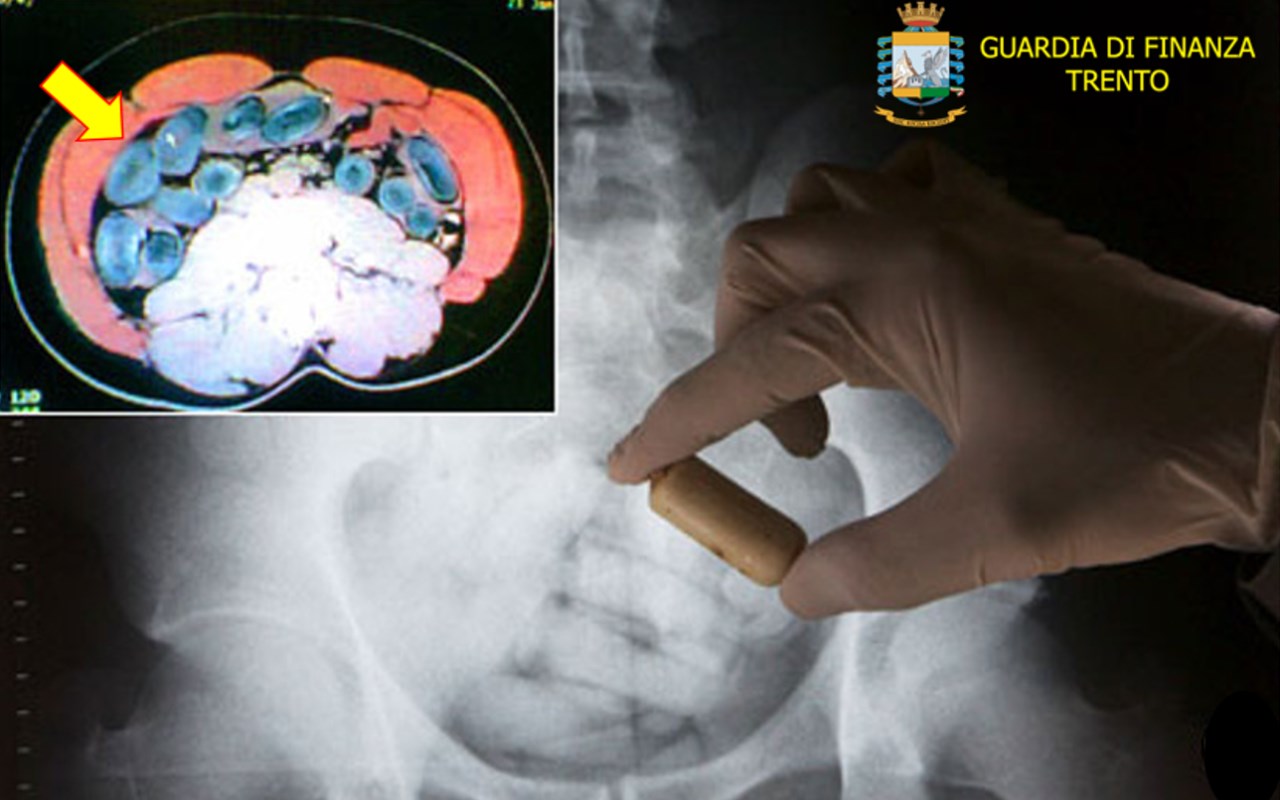

Un’operazione anti droga è stata messa a segno dalla Guardia di Finanza di Trento. A finire in manette è stato un corriere nigeriano di 26 anni in viaggio verso Verona sul treno Monaco-Bologna. Aveva in pancia 76 ovuli contenenti un chilo di eroina. E’ stato fiutato dal cane antidroga della delle Fiamme Gialle. Il giovane era sceso dal treno per fumarsi una sigaretta durante alcuni minuti di sosta del treno alla stazione di Trento. Il ragazzo è stato seguito dai finanzieri e scovato all’interno della toilette del treno, dove si era nascosto. Il giovane, residente regolarmente in Italia e domiciliato in provincia di Avellino, è stato processato per direttissima. Ora si trova in carcere a Verona. [fm] (Foto: guardia di finanza di Trento)

TRENTO. CORRIERE BLOCCATO SUL TRENO: 76 OVULI IN PANCIA